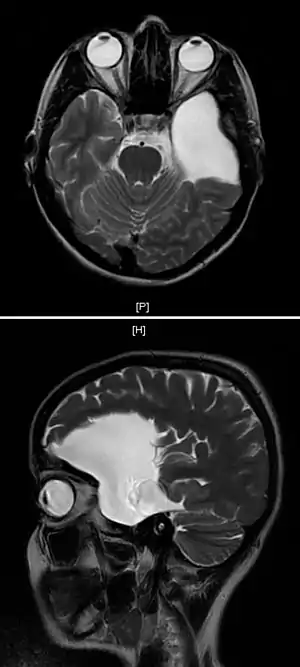

An MRI of a 25-year-old woman with left frontotemporal arachnoid cyst.